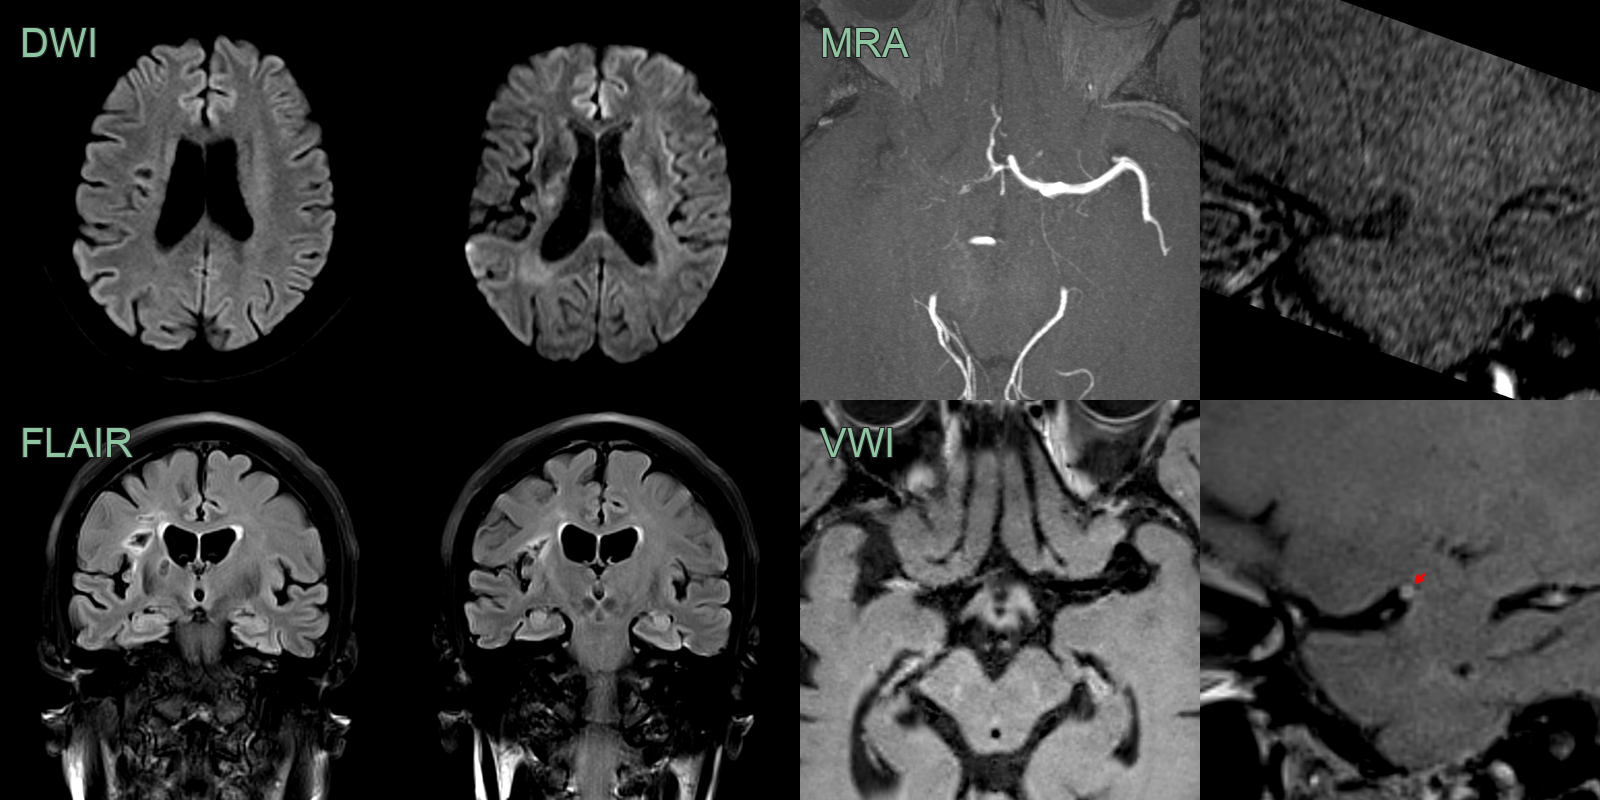

Varicella Zoster Virus (VZV) Vasculitis

- 50-year-old patient presented with visual disturbance and left sided weakness.

- CSF PCR was positive for VZV.

- MRI showed multiple left MCA territory infarcts.

- There wasthick eccentric enhancement on the right MCA but no stenosis initially.

- After 5 months and following steroid therapy, the enhancement associated with the vasculopathy regressed but a severe long segment stenosis developed. This only slightly improved (trace of flow related signal) on further follow-up MRA (not shown).